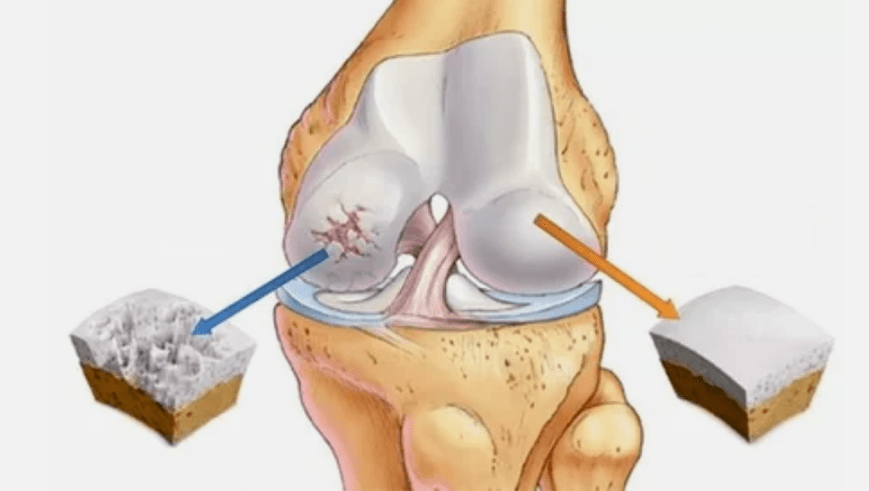

The joints act for a long time, initially affecting only the clear cartilage, and then spreading to the bones, involving the synovial shell, muscles and the entire joint capsule.In the first or early stages of arthritis, the lesions show slightly: pain, swelling, and redness of the skin after hard work.The peak in the morning dropped due to the ignorance of uncomfortable sensations, joint deformation, inflammation, and severe pain.The disease is characterized by the loss of pain after joint development.Without treatment, a person will completely lose the mobility of the joints.

Pathology exists due to regenerative function, immunity or mechanical damage.It becomes thinner for various reasons of cartilage.Under normal circumstances, cartilage fabrics will receive enough nutrients to recover, but the fabric does not have time to regenerate due to excessive physical fatigue or due to violation of metabolic processes.In the first stage, joint mobility remains.Given what joint is a definition, it is worth adding pathological development in more detail.

- The main lesions affect the hyacinth cartilage.In the case of circulatory diseases, pathological deterioration occurs.This is the first step or cause of arthritis.

- Hyaluronic coating pathology.Thinning of cartilage leads to substituting its pathological tissue - bone structure.

- Abnormal growth occurs on cartilage-bone plants.

- Overload invading healthy cartilage areas due to the natural anatomy of the cartilage and bones.Untreated joint tissue destruction is evolving and leading to disability.

When the degree of disease increases, the pathological process will still intensify.Finally, all the clear cartilage is destroyed.